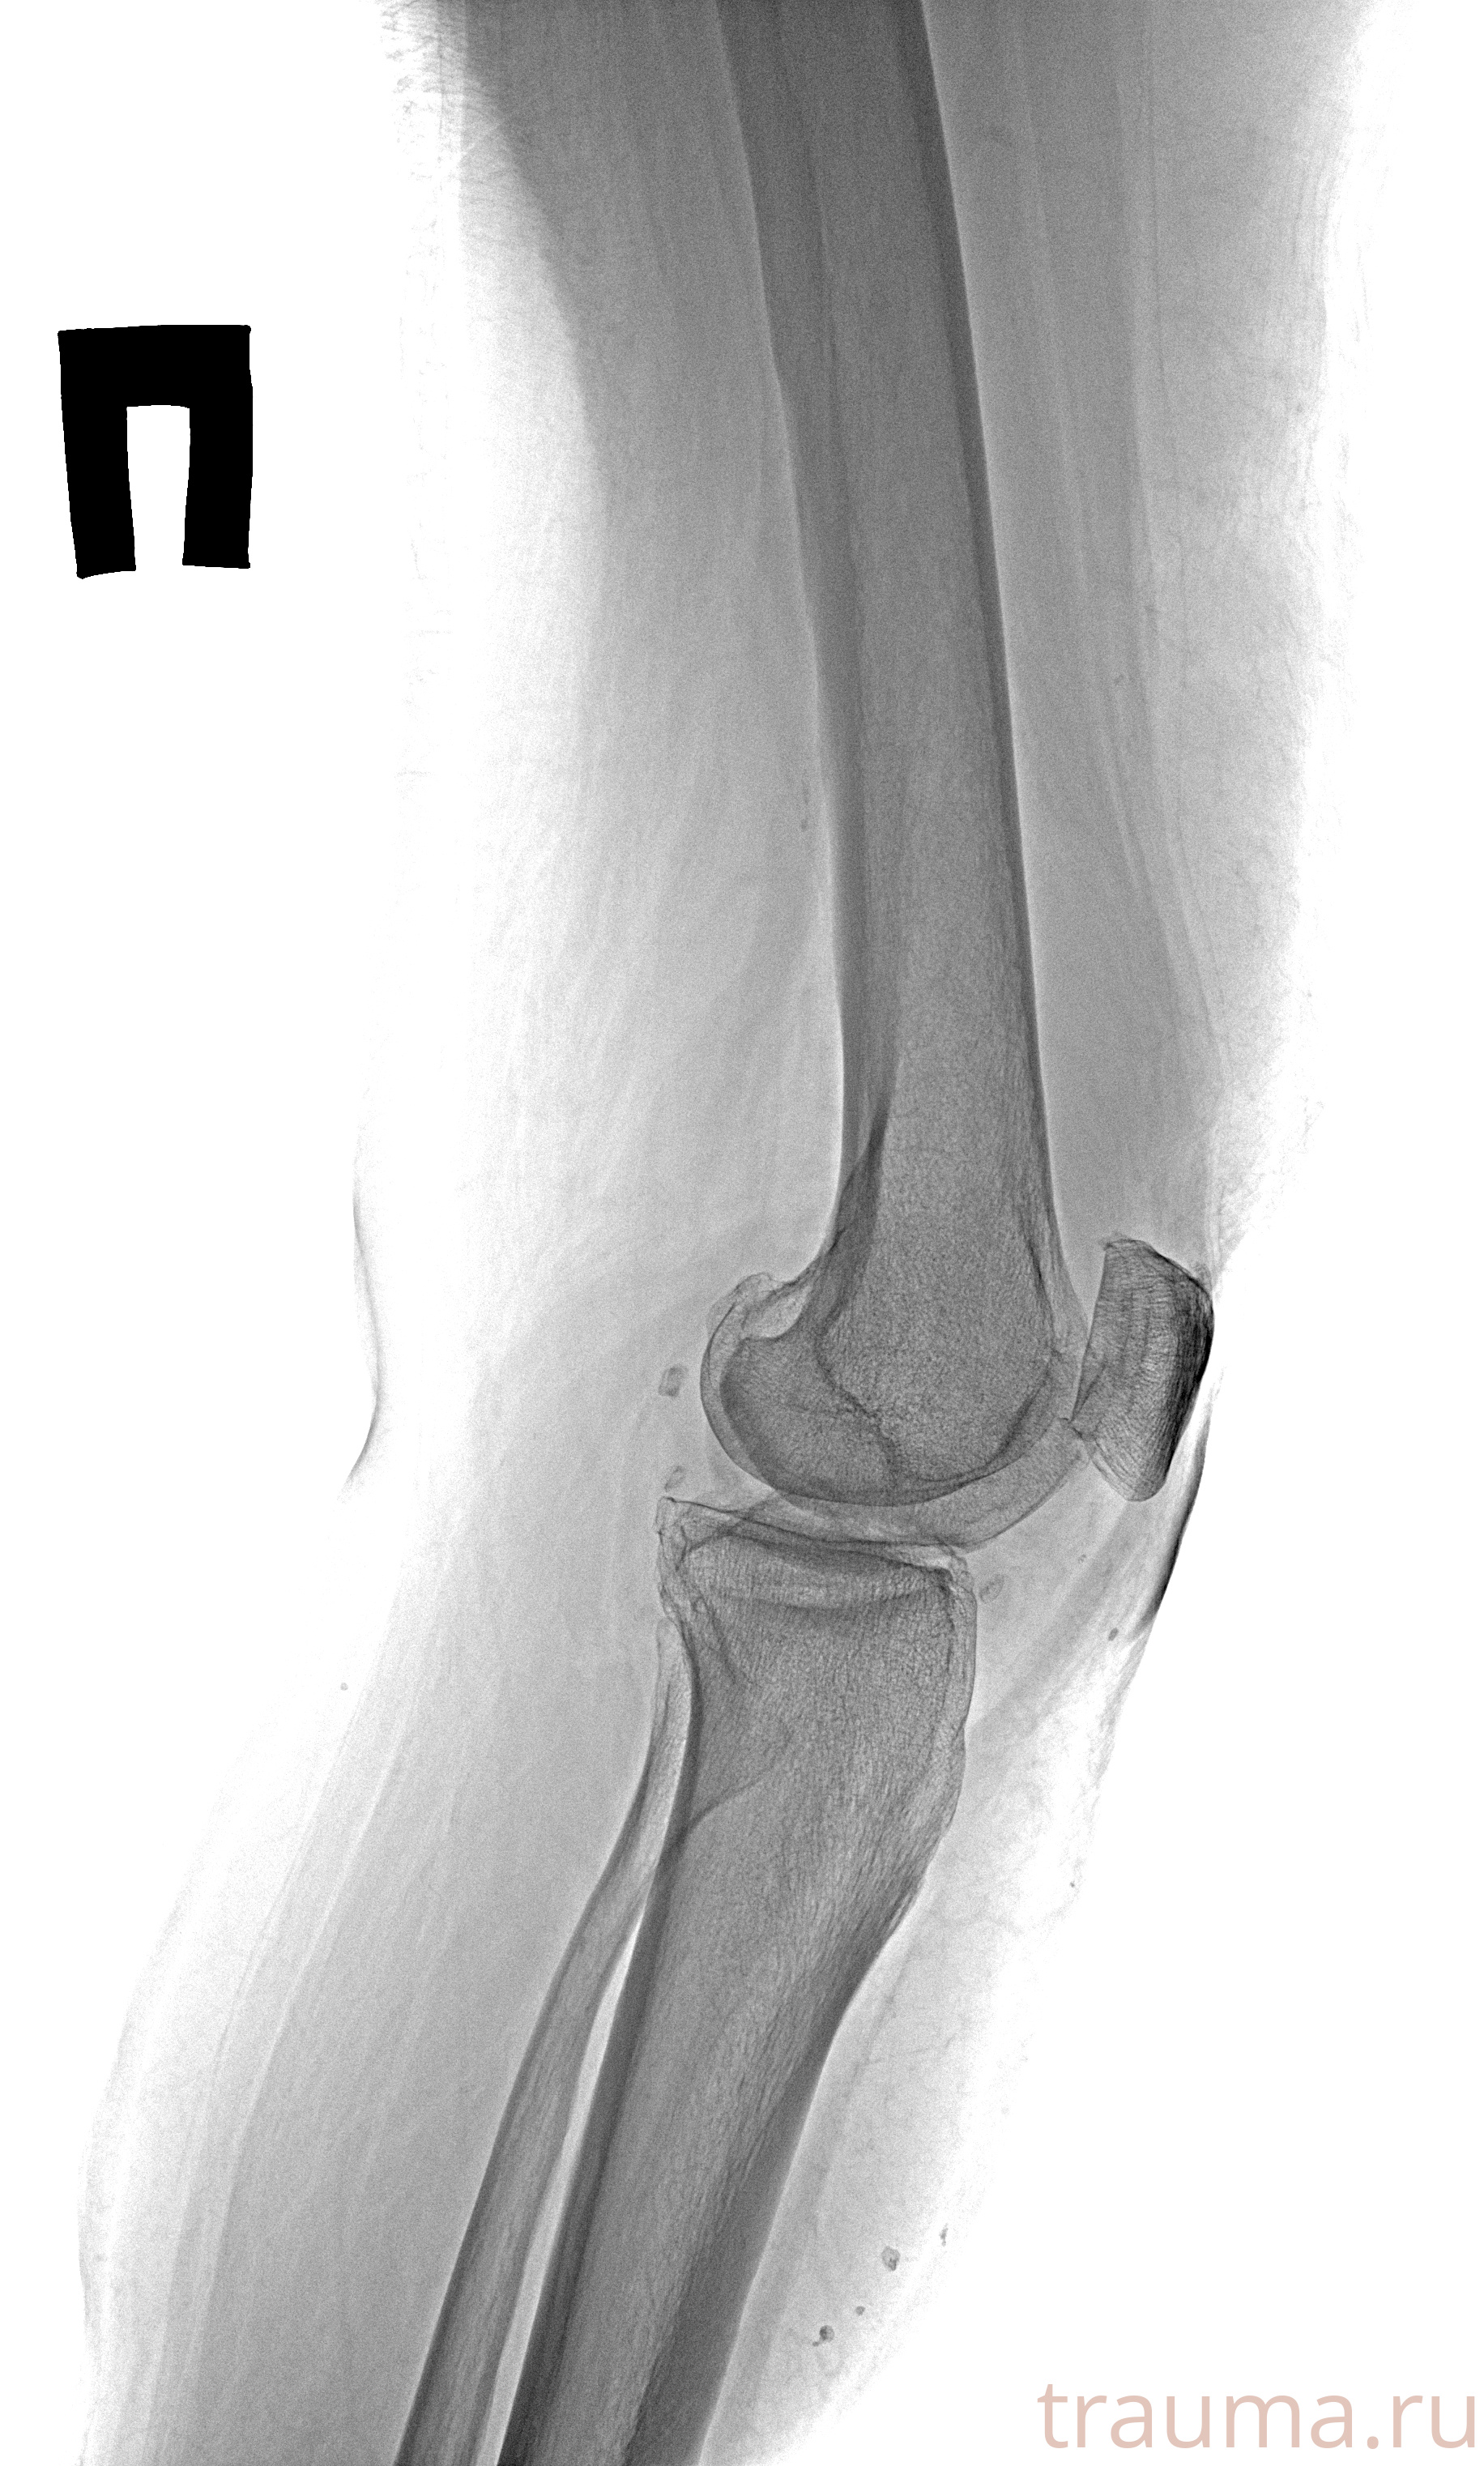

Рентген на дому: по вашему адресу приезжает врач-рентгенолог, травматолог-ортопед с мобильным рентгеновским аппаратом, проводит диагностику травмы или заболевания, делает необходимые рентгенограммы, дает рекомендации по дальнейшему лечению. Получить качественные снимки в домашних условиях возможно благодаря уникальной методике, разработанной МосРентген Центром для института  Склифосовского